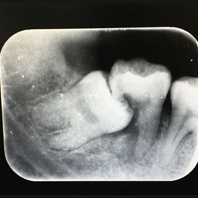

病症:磨牙,其次为上颌尖牙,第二双尖牙和额外牙等,有时有双侧的埋伏牙。一般由X光片检查发现

口腔疾病牙齿萌出期已过而仍在颌骨组织中未能萌出的牙齿称为埋伏牙(embeded teeth)。埋伏牙可对相邻的牙齿产生压迫症状,如第二磨牙受埋伏的第三磨牙压迫,发生牙根吸收,引起疼痛并继发牙髓炎和根尖周炎。2.萌出障碍因邻牙畸形、乳牙早失使间隙缩小,额外牙的阻碍、幼儿期颌骨感染或外伤等所致。3.全身性因素遗传因素或内分泌障碍,如锁骨、颅骨发育不全症患者常有多个埋伏牙。埋伏牙与其周围组织之间存在牙囊组织,一般是无炎症的。埋伏牙有一种向牙齿胎面及切端方向移动的自然趋势,遇到阻碍时则产生压力。